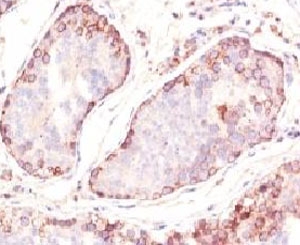

Recognizes a protein of 42-46kDa, identified as MAGE-1. This mAb does not cross-react with other members of MAGE-family. Human malignant neoplasms carry rejection antigens that are recognized by the patients' autologous, tumor directed and specific, cytolytic, CD8+ T lymphocyte clones (CTL). The MAGE family of genes codes an important group of antigens. It was identified that melanomas and primary glial brain tumors express common melanoma associated antigens (MAAs). Because MAGE-1 is expressed on a significant proportion of human neoplasms of various histological types (melanoma, brain tumors of glial origin, neuroblastoma, non-small cell lung cancer, breast, gastric, colorectal, ovarian, renal cell carcinomas) and not on normal tissues, the encoded antigen may serve as a marker of early detection and target for cancer immunotherapy.

1. Staining of formalin-fixed tissues requires boiling tissue sections in pH 9 10mM Tris with 1mM EDTA for 10-20 min followed by cooling at RT for 20 min.

2. The prediluted format is supplied in a dropper bottle and is optimized for use in IHC. After epitope retrieval step (if required), drip mAb solution onto the tissue section and incubate at RT for 30 min.